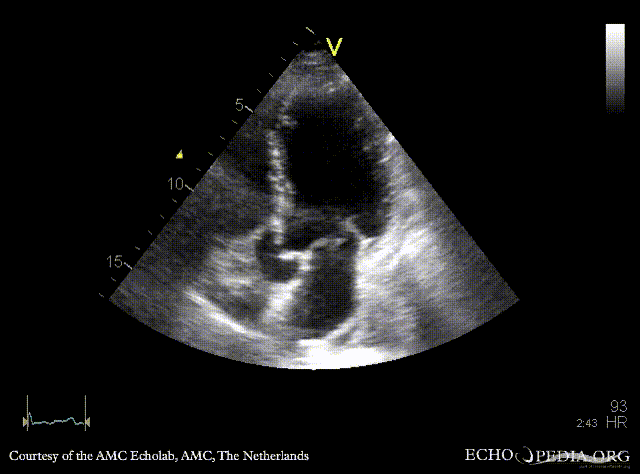

| PSAX: mobile fragment of papillary muscle | A5CH |

| A2CH | A4CH: severe mitral regurgitation, excentric jet |